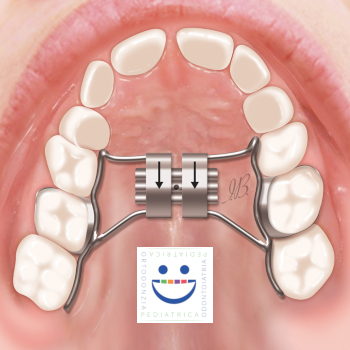

Tra i possibili apparecchi, il più comunemente utilizzato è l’espansore palatale. E’ un dispositivo fisso composto da due anelli, chiamati bande, ancorati ai denti posteriori, e uniti da una struttura in acciaio con una vite al centro. Durante il primo periodo successivo all’applicazione, questa vite dovrà essere girata dai genitori con un’apposita “chiavetta” secondo le indicazioni fornite dall’ortodontista, per provocare l’espansione delle ossa del palato.